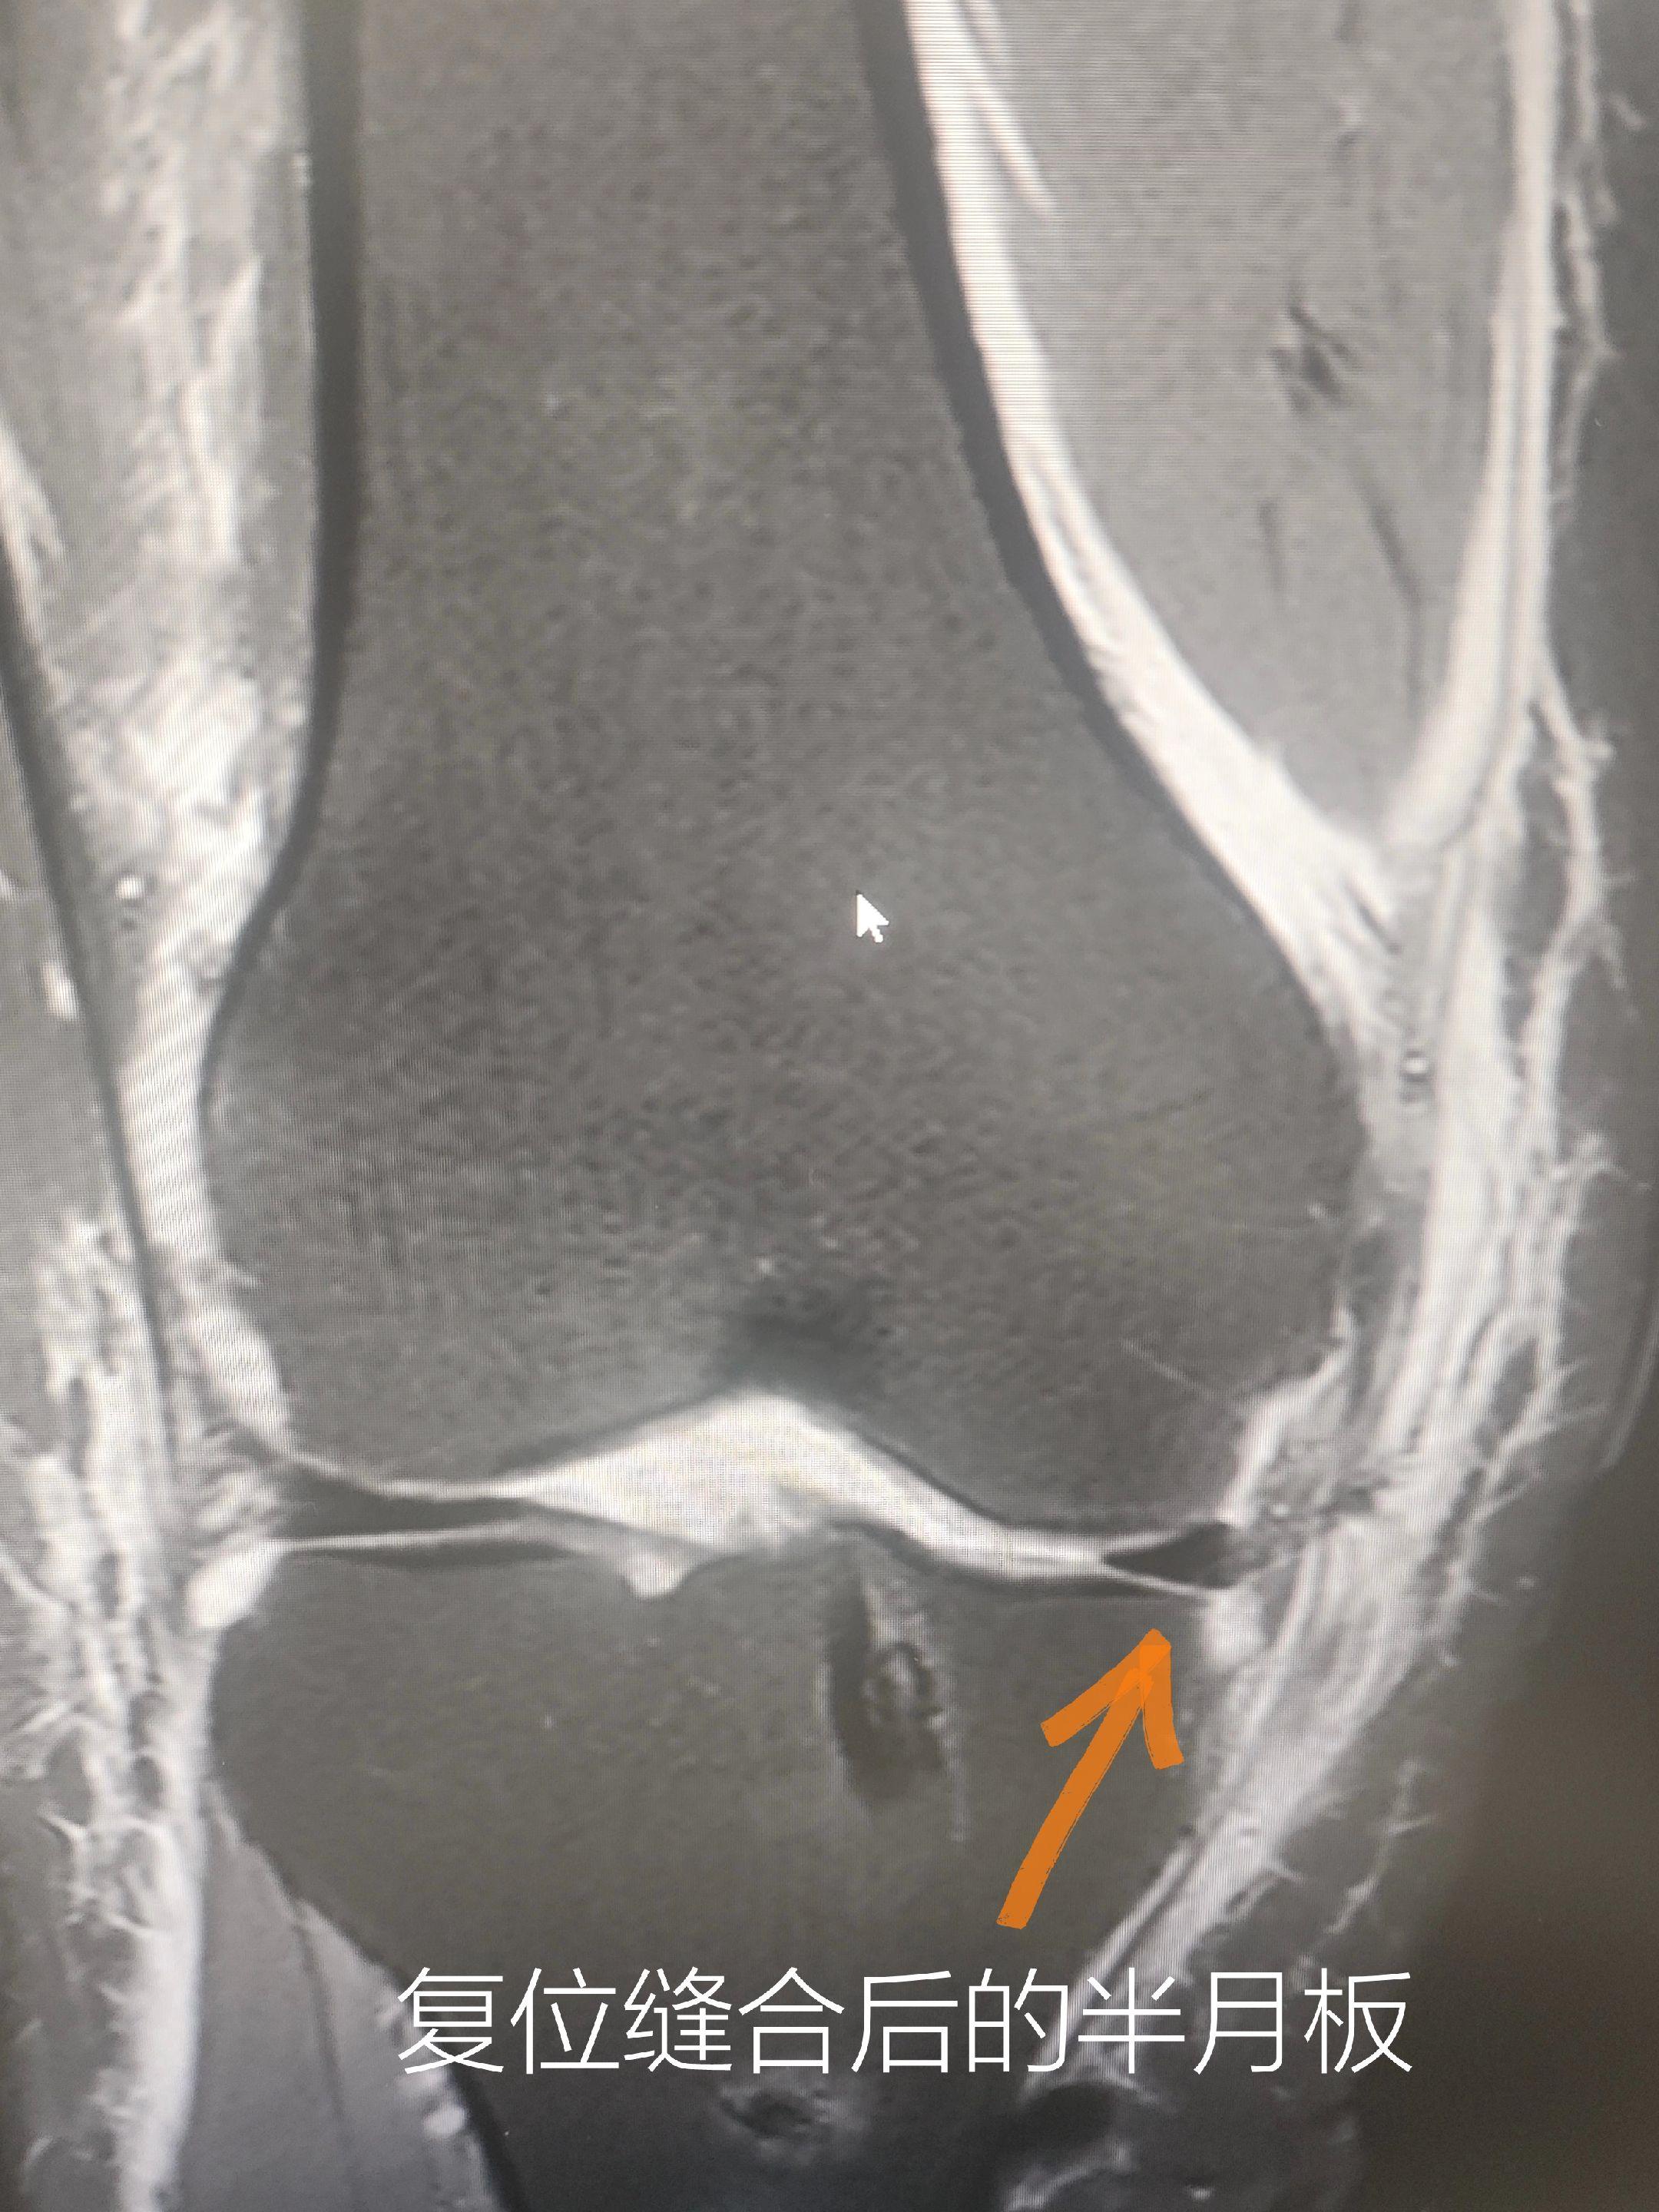

膝关节前十字韧带重建+半月板缝合。